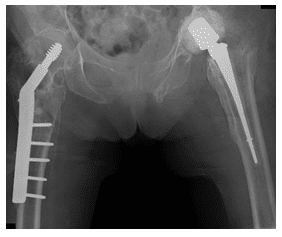

X-Ray shows osteoporosis with prosthetic left hip and right hip internal fixation, along with nondisplaced fracture of the right ischium

X-Ray show post-operative right hip ORIF and left hip ORIF with a spacer device placement in left hip